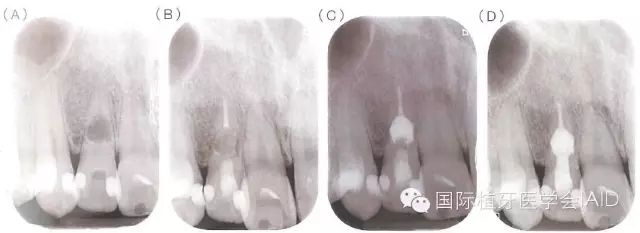

牙根內(nèi)吸收若是早期發(fā)現(xiàn),在未與牙周組織相通的情況下治療步驟相對單純以徹底去除導(dǎo)致牙髓腔內(nèi)感染與內(nèi)吸收窩洞內(nèi)的肉芽組織為首要目標(biāo),可運(yùn)用機(jī)械性的清創(chuàng)配合次氯酸鈉溶液與超聲波器械的沖洗,加強(qiáng)清創(chuàng)效果,之后于根管內(nèi)放置氫氧化鈣至少1~2周,在無臨床癥狀下,便能以古塔膠熱塑性封填系統(tǒng)(warmgutta percha technique)或是三氧礦化物(MTA,mineral trioxide aggregate)進(jìn)行根管封填;但若此內(nèi)吸收為與外界相通的牙根吸收病灶,由于MTA具有良好的密封能力(sealingability)及生物兼容性(biocompatibility)會是更恰當(dāng)?shù)倪x擇(下圖)。

(A)31歲男性因牙位12顏色改變求診,該牙無臨床癥狀,但X光檢查發(fā)現(xiàn)在牙根中段有一個約4.5*5mm的橢圓形呈放射線透性影像,檢查時牙髓組織已無活性反應(yīng)并診斷為牙根內(nèi)吸收。(B)于顯微鏡下進(jìn)行根管治療,根管內(nèi)有出血現(xiàn)象且有肉芽組織沾粘于管壁,懷疑病灶與根管外相通,移除發(fā)炎組織后進(jìn)行根管清創(chuàng)搭配超音波器械沖洗,并放置氫氧化鈣。根管封填分兩部份進(jìn)行,先以古塔膠填充填下半部根管;(C)以MTA充填于吸收窩洞,確認(rèn)MTA硬化后,以復(fù)合樹脂填補(bǔ)根管開口;(D)根管治療完成后一年的追蹤,該牙無癥狀且周邊組織愈合良好。